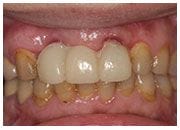

陳女士是上市公司的董事長夫人,時常需要交際應酬,但是前牙的假牙讓她困擾許久,希望尋求自然又美觀的假牙,最後於本診所接受人工植牙的治療,並且使用全瓷牙冠,效果自然,與其他牙齒極為搭配,讓人分辨不出真牙或假牙,陳女士有喝茶的習慣,特別要求假牙顏色不能死白,必須與所有牙齒一致,最後的結果令陳女士相當滿意。

治療前

治療中

治療後